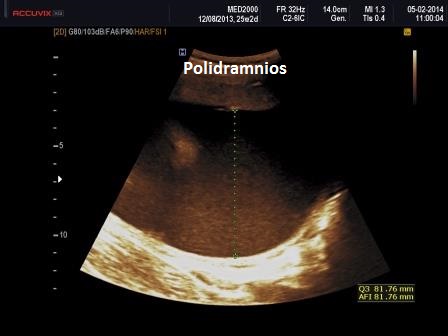

Le lesioni caratteristiche a carico del SNC sono rappresentate  da idrocefalo grave, con ventricoli aperti nello spazio subaracnoideo, ipoplasia cerebrale, anomalie della linea mediana e del setto pellucido (agenesia del corpo calloso); possono essere presenti encefalocele occipitale, una caratteristica conformazione del forame magno “key-hole shaped”, mandibola piccola e naso malformato, labio-palatoschisi. Caratteristica è la polidattilia postassiale alle mani e preassiale ai piedi (l'alluce duplice è altamente caratteristico, quasi esclusivo, di questa condizione morbosa). Segnalati anche piede torto e difetti cardiovascolari (difetti del setto atriale; atrio unico). Come ha segnalato lo studio di Salonen e coll. (1981) condotto su 28 neonati di 18 famiglie, l'esito abituale della gravidanza è la nascita di feto morto o morte in epoca neonatale.

La Diagnosi Prenatale si basa su: 1) assenza di movimenti attivi fetali; 2) polidattilia postassiale alle mani; 3) polidattilia preassiale ai piedi;  4) idrocefalia; 5) polidramnios.